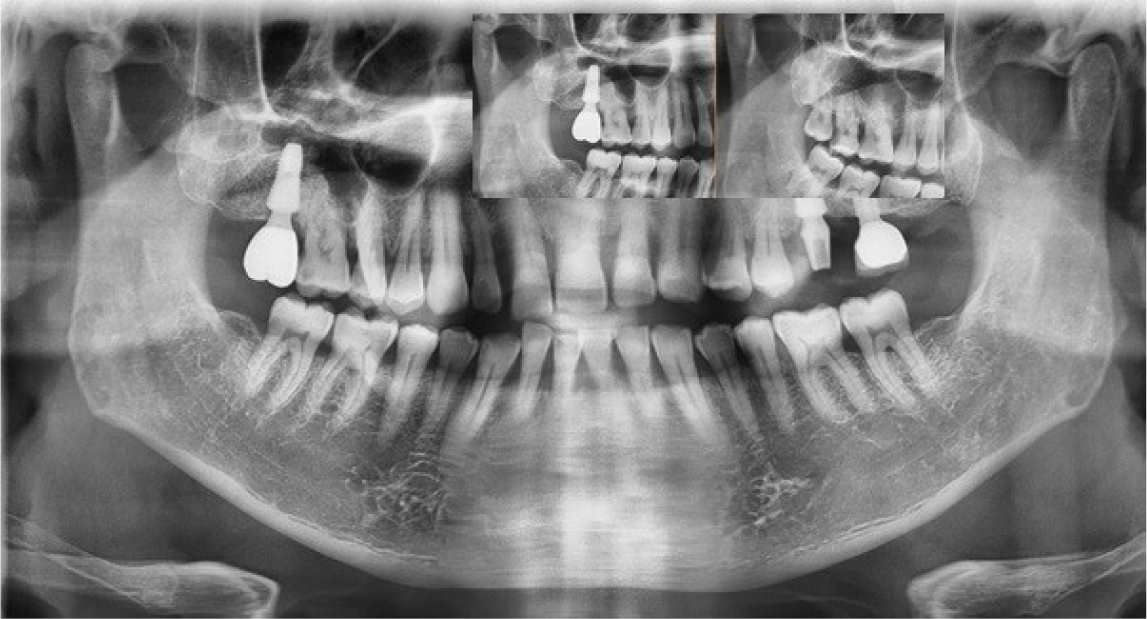

After the stuffy nose on the right side was completely gone, the bony window was extended anteriorly and the sinus membrane around perforated area was lifted. The perforated membrane was sutured (Rexlon nylon 4-0®; SM eng, Seoul, Korea) and the collagen wound dressing was inserted for the complete sealing (Fig. 5). Alloplastic bone-grafting material (A-oss®; Osstem implant Co., Seoul, Korea) was packed and the implant placement (Superline®; Dentium implant Co., Seoul, Korea) was performed immediately (Fig. 6). After operation, conservative treatment (augmentin 625 mg, acidified pseudo ephedrine HCL 2.5 mg, acetaminophen 500 mg, 3 times daily) continued for 1 week. After one week, the suture was removed and the discomfort symptom was disappeared. After 3 months later, occlusal loading started (Fig. 7). In the 3-months follow-up, the implant and lifted sinus bone formation were stable (Fig. 8). In the 2-years follow-up, the implant was left stable and the sinus lifted bone was maintained well (about 6 mm height) (Fig. 9).

In this study, the author performed simultaneous implantation, although there was perforation. The repair technique may be vary depending on the size of the membrane perforation. If a membrane perforation is <2 mm in diameter, it is not typically cause for concern and will not usually require any special treatment.16 If the perforation is larger, it needs to be closed and covered to prevent loss of the graft and secondary complication such as sinusitis.17 In large perforation, the collagen membrane that covered the perforation could not be supported by surrounding intact sinus membrane. Therefore it is impossible to maintain the position of the collagen membrane. Large membrane perforations often require complex repairs.18,19 Various methods can be used for the treatment of membrane perforation. In case of small perforation (<5 mm), the perforated membrane can be managed by using tissue fibrin glue, suturing or by covering it with a restorable barrier membrane. In case of large perforation (>5 mm), larger barrier membranes, lamellar bone plates or suturing either alone or in combination with fibrin glue can be used.12 In this case, the perforated membrane was repaired with suture and collagen wound dressing. Many authors did not recommend membrane suturing technique because of the extremely delicate features of the membrane. Also, the suture of the membrane can be enlarge the existing perforation or create a new one.18 And as in this case, the window can be opened wider and the membrane should be lifted wider in the process of approaching and preparing for suture. But if the approach is possible and the membrane is not too thin, suturing technique is an easy way to recover the membrane perforation. In this case, the size of the perforation was about 5mm in the first operation. The membrane was repaired with collagen wound dressing. However, infection occurred in the perforated area. In order to shorten the treatment period and for the management of the patient, the infection source and implant were removed, and at the same time, the sinus membrane repair using suture (Rexlon nylon 4-0®; SM eng, Seoul, Korea) was performed.20 The suturing membrane was used successfully for the closure of the perforation and dental implant was placed simultaneously. There were no serious infections. And clinical and radiographic findings at the 2-year follow up were adequate (Fig. 9).